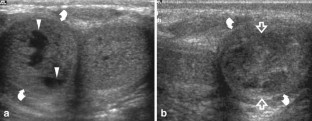

Injury to the penis may result from penetrating or nonpenetrating trauma. Nonpenetrating injury to the erect penis can produce albugineal tear, intracavernous hematoma or extraalbugineal hematoma from rupture of the dorsal vessels. Nonpenetrating injury to the flaccid penis usually follows blunt perineal traumas producing extratunical or cavernosal haematomas, or cavernosal artery tear followed by high flow priapism. Differential diagnosis between albugineal tear and other penile injuries must be obtained as soon as possible, since early surgical repair of albugineal tear reduces significantly the rate of postraumatic curvature and fibrosis. Ultrasonography (US) is able to detect the exact site of the tear in most patients as an interruption of the thin echogenic line of the tunica albuginea. Other imaging techniques are rarely required in the clinical practice. Color Doppler US is the imaging modality of choice to evaluate patients with high flow priapism. Focal or diffuse cavernosal fibrosis can be identified with US as echogenic areas in the cavernosal bodies. Postraumatic erectile dysfunction can result from fibrotic changes, nerve and vascular impairment or both. Doppler evaluation of penile vasculature is required in young patients with postraumatic impotence before surgical revascularization procedures.

Fig. 1

Fig. 2